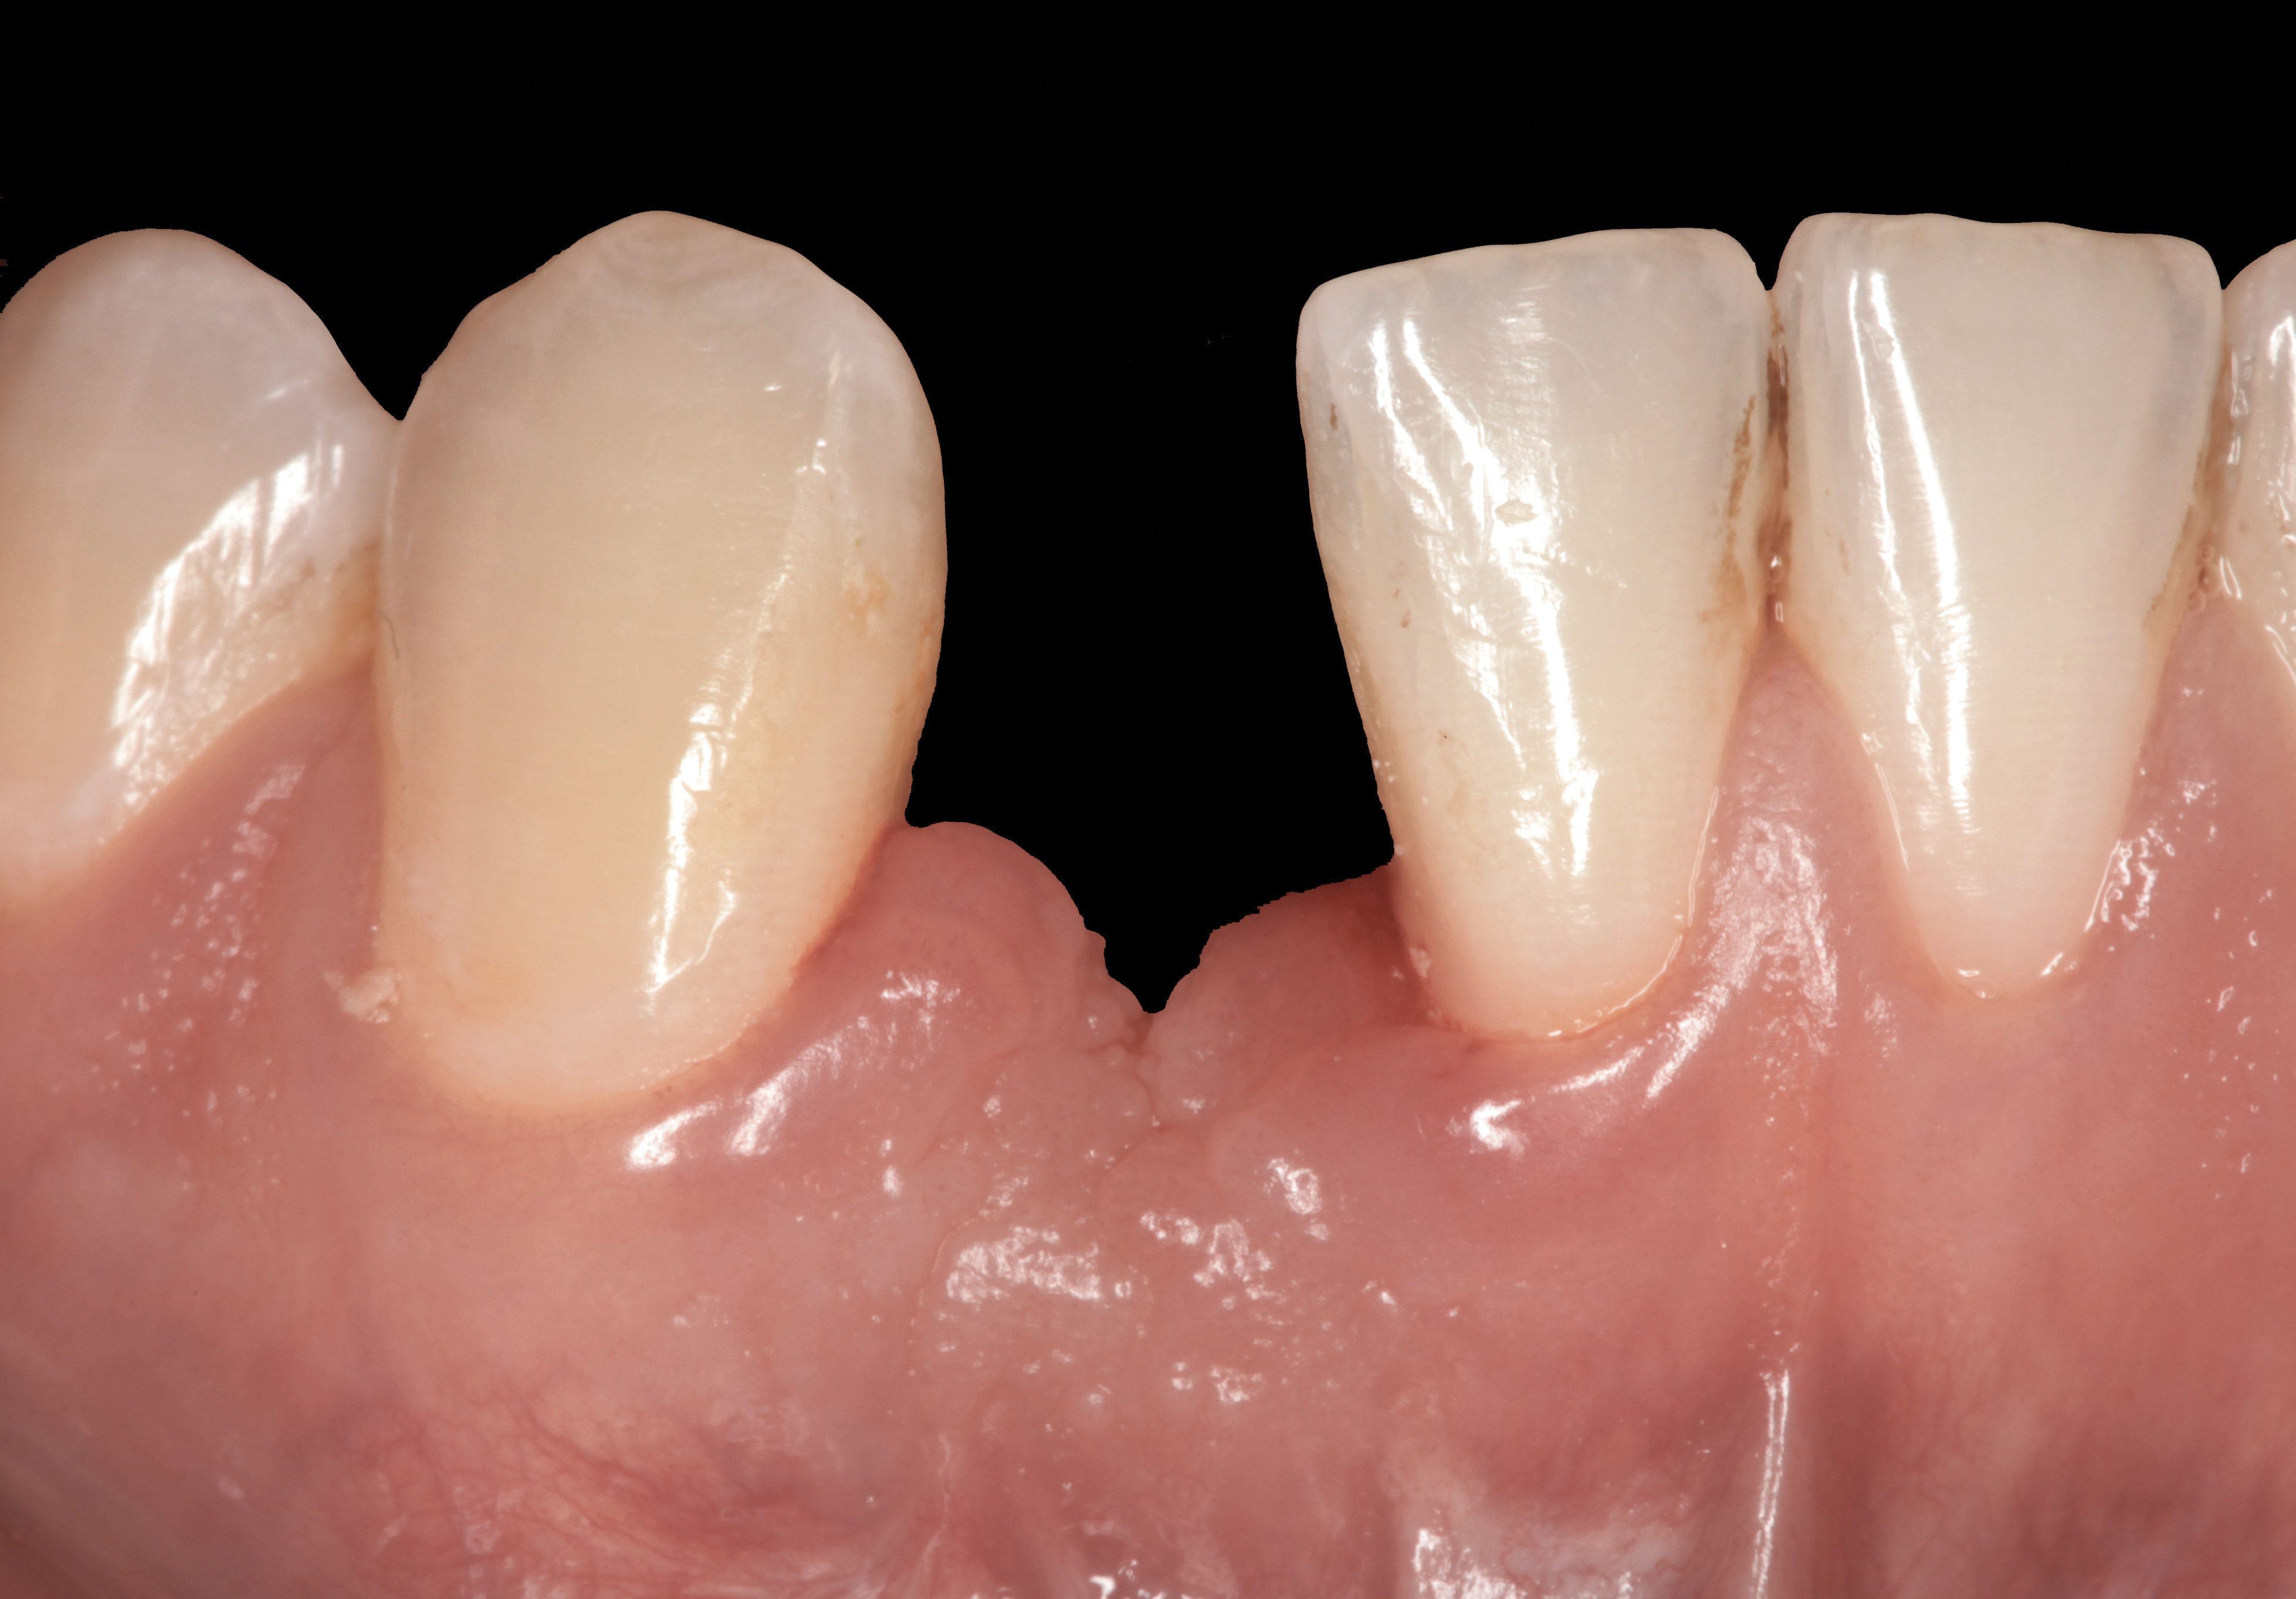

Problem: The implant is placed too facial with significant recession on the midfacial aspect of the abutment and/or crown; the implant is healthy and the patient has a high smile line with an intermediate to thick periodontal phenotype (Figure 1 and Figure 2).17-19

Fig 1. Midfacial recession can affect the esthetics of a smile and lead to an unsatisfactory outcome.

Fig 2. The cause for midfacial recession is excessive labial implant placement. Secondary to poor placement is overcontouring of the implant abutment.

Fig 3. A patient presented with a high smile line and midfacial recession of the maxillary right lateral incisor as evidenced by the increased tooth length compared with the contralateral lateral incisor.

Fig 4. Intraoral view of tooth No. 7 with the gingival zenith more apical than the adjacent central incisor and canine tooth.